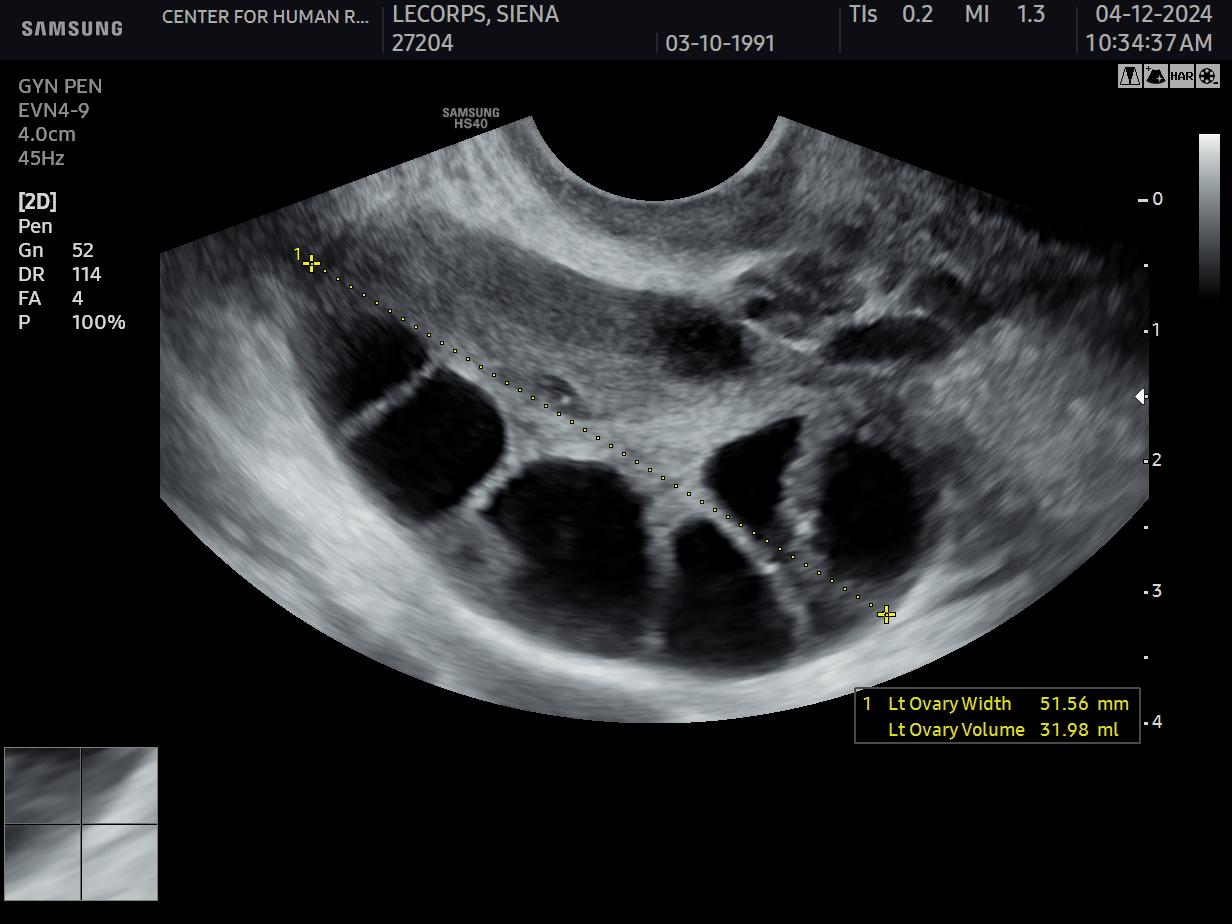

This month’s images portray a circumstance rather rarely addressed by either researchers or clinicians: while pretty-much everybody understands that in ovaries eggs develop within follicles, far less appreciated is the fact that muscular forces participate in follicular growth and egg maturation. This subject, nevertheless, has recently been attracting increasing attention, as we learn to confront the many factors underwriting why– especially as a function of a woman’s age–human eggs are variable in their quality. What investigators at the CHR have been able to visualize, indeed, offers interesting new insights:

Image 1 shows the appearance of a young ovary labeled to show in white the distribution of muscle cells. Note the follicle in the center of the field and the pronounced bands of muscle tissue creating a swirling like configuration that encloses smaller follicles (circles) near the bottom of the image. If we manipulate this image to emphasize only those cells resembling muscle, you see what is displayed in Image 2. The red fibers coursing around the follicles and through the ovarian tissue emphasize what we now believe reflects active force generation that likely is highly regulated as follicles are selected and prepared for ovulation during natural or stimulated cycles.